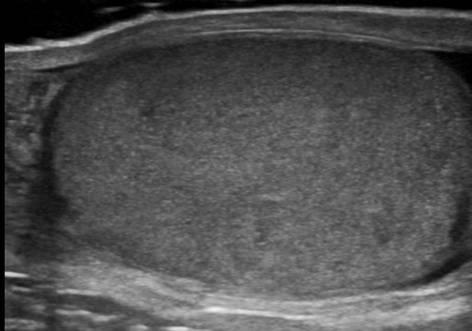

Viêm tinh hoàn - mào tinh

Viêm tinh hoàn – mào tinh

» Thông tin: Nam giới – 34 tuổi.

» Lâm sàng: Sưng đau vùng bìu.

# Tăng kích thước và tín hiệu mạch trên doppler tinh hoàn và mào tinh hoàn.